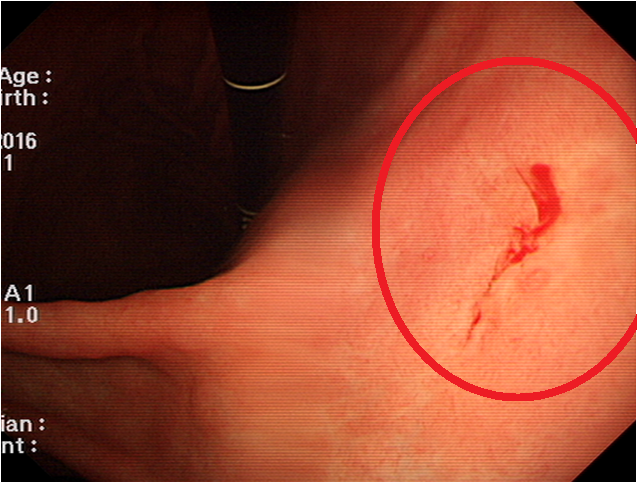

위에서 출혈이 발생하면 대변이 **검붉거나 까맣고 끈적한 형태(흑변)**로 나올 수 있습니다.

이는 위 출혈의 주요 신호이며, 위암이 진행 중일 가능성이 있으므로

한 번이라도 이런 대변을 본다면 즉시 병원을 방문해야 합니다.

위암 초기에는 눈에 띄는 출혈 없이도 지속적으로 피를 잃는 경우가 있어 주의가 필요합니다.9. 식후 구토물에 피가 섞임

심한 경우 구토 시 커피색 또는 선홍빛 피가 섞여 나오는 경우가 있습니다.

이는 위 점막이 심각하게 손상되었거나 암 덩어리로 인해 출혈이 생긴 경우이며, 즉시 응급 처치가 필요합니다.